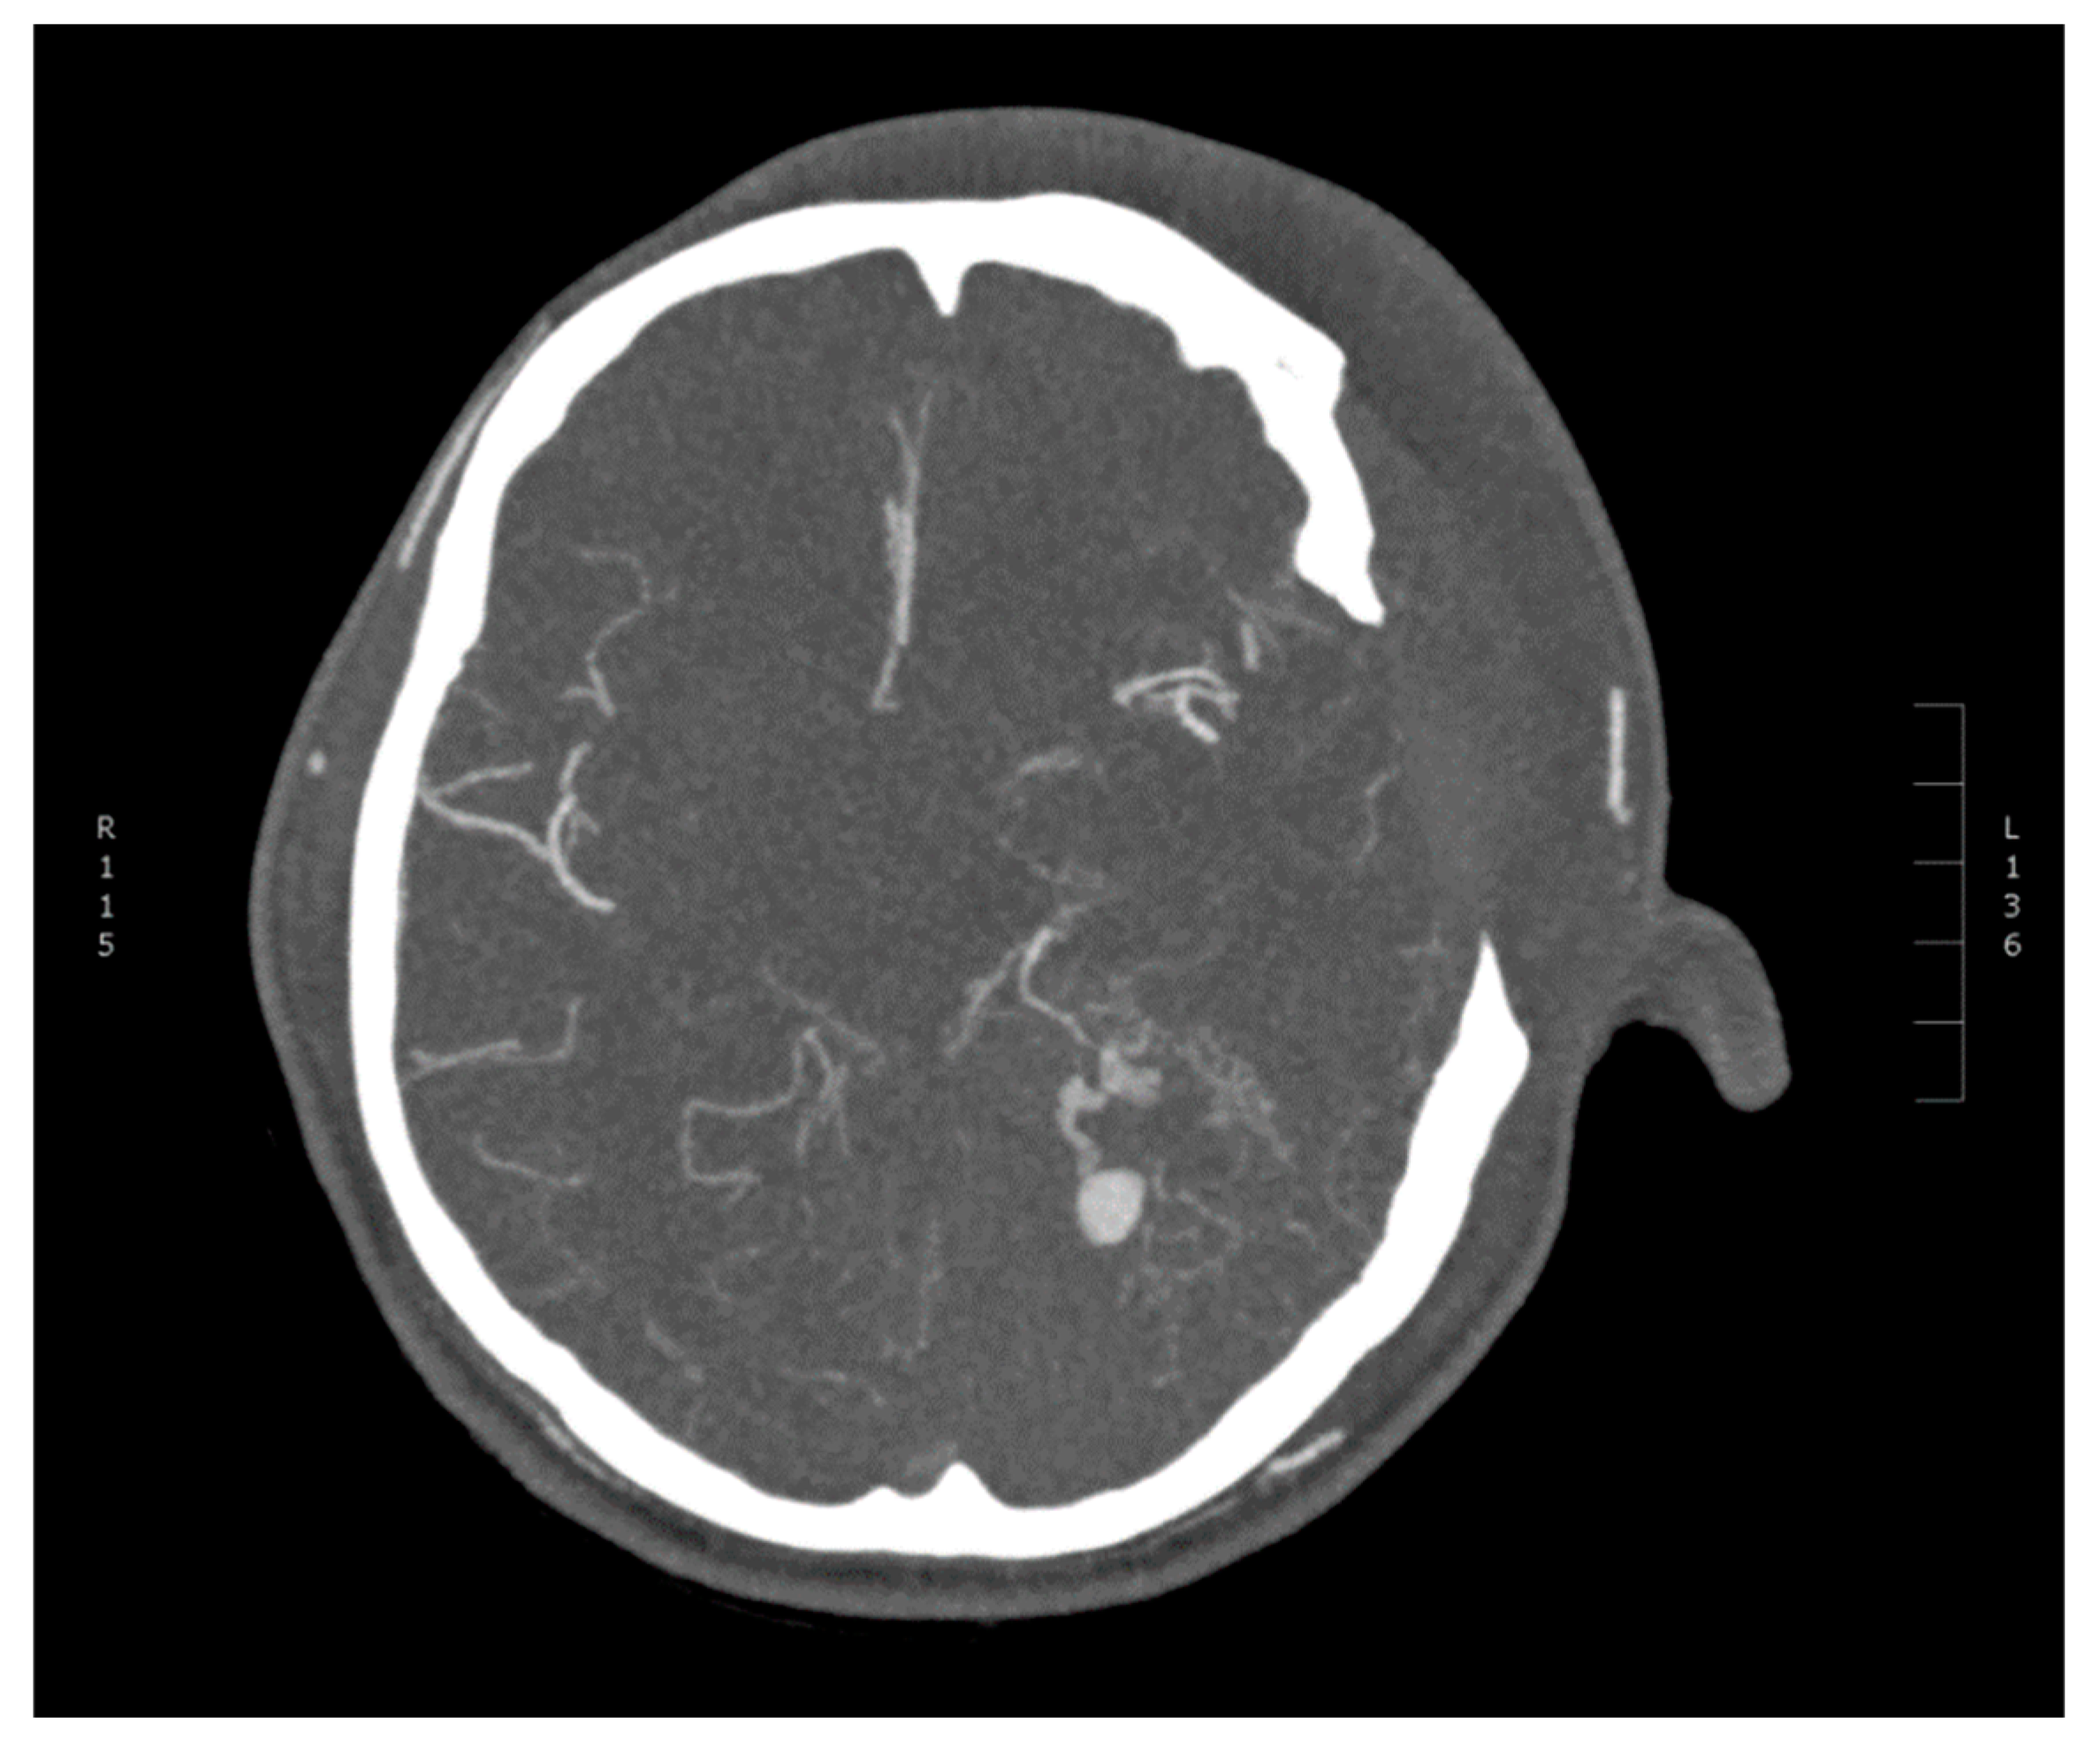

2. Case Report